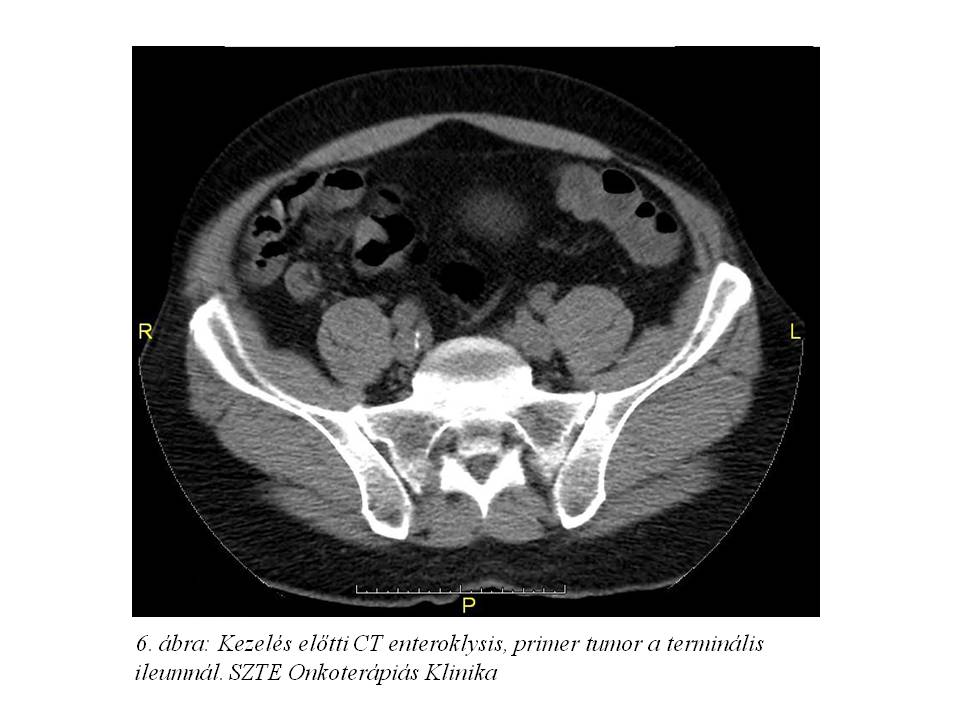

Tekintettel a diagnózis óta eltelt több hónapra re-staging hasi MR (4. ábra) és CT enteroklysis vizsgálat (5. ábra, 6. ábra, 7. ábra) történt. Az előbbi változatlan állapotot írt le, azonban az utóbbin a terminális ileum kezdeti szakaszán kb. 1,1x1,8x10 mm-es térszűkítő folyamat is ábrázolódott, mely megfelel a primer neuroendokrin tumornak.